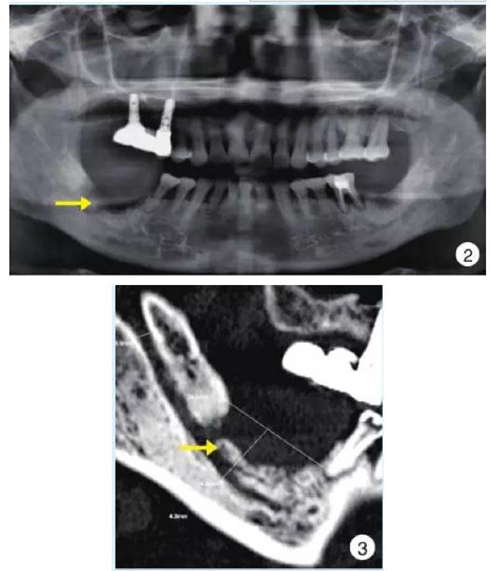

影像學早期無明顯變化,后期典型表現(xiàn)為局部片狀骨密度增高影以及不規(guī)則的骨吸收影像、死骨形成,偶爾可見骨膜反應;伴病理性骨折時可見骨折線。

2.jpg